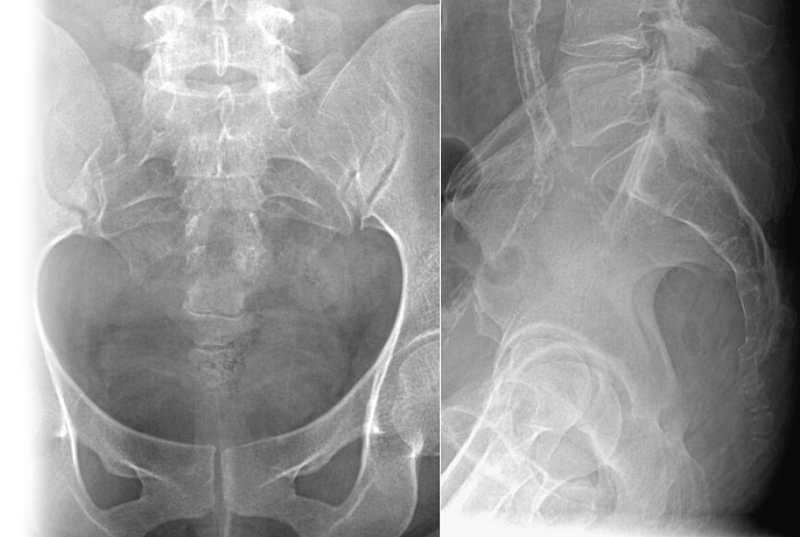

Рентгенография копчика – важный метод прицельного исследования, который позволяет оценить состояние копчика.

Диагностическая услуга выполняется в двух проекциях.